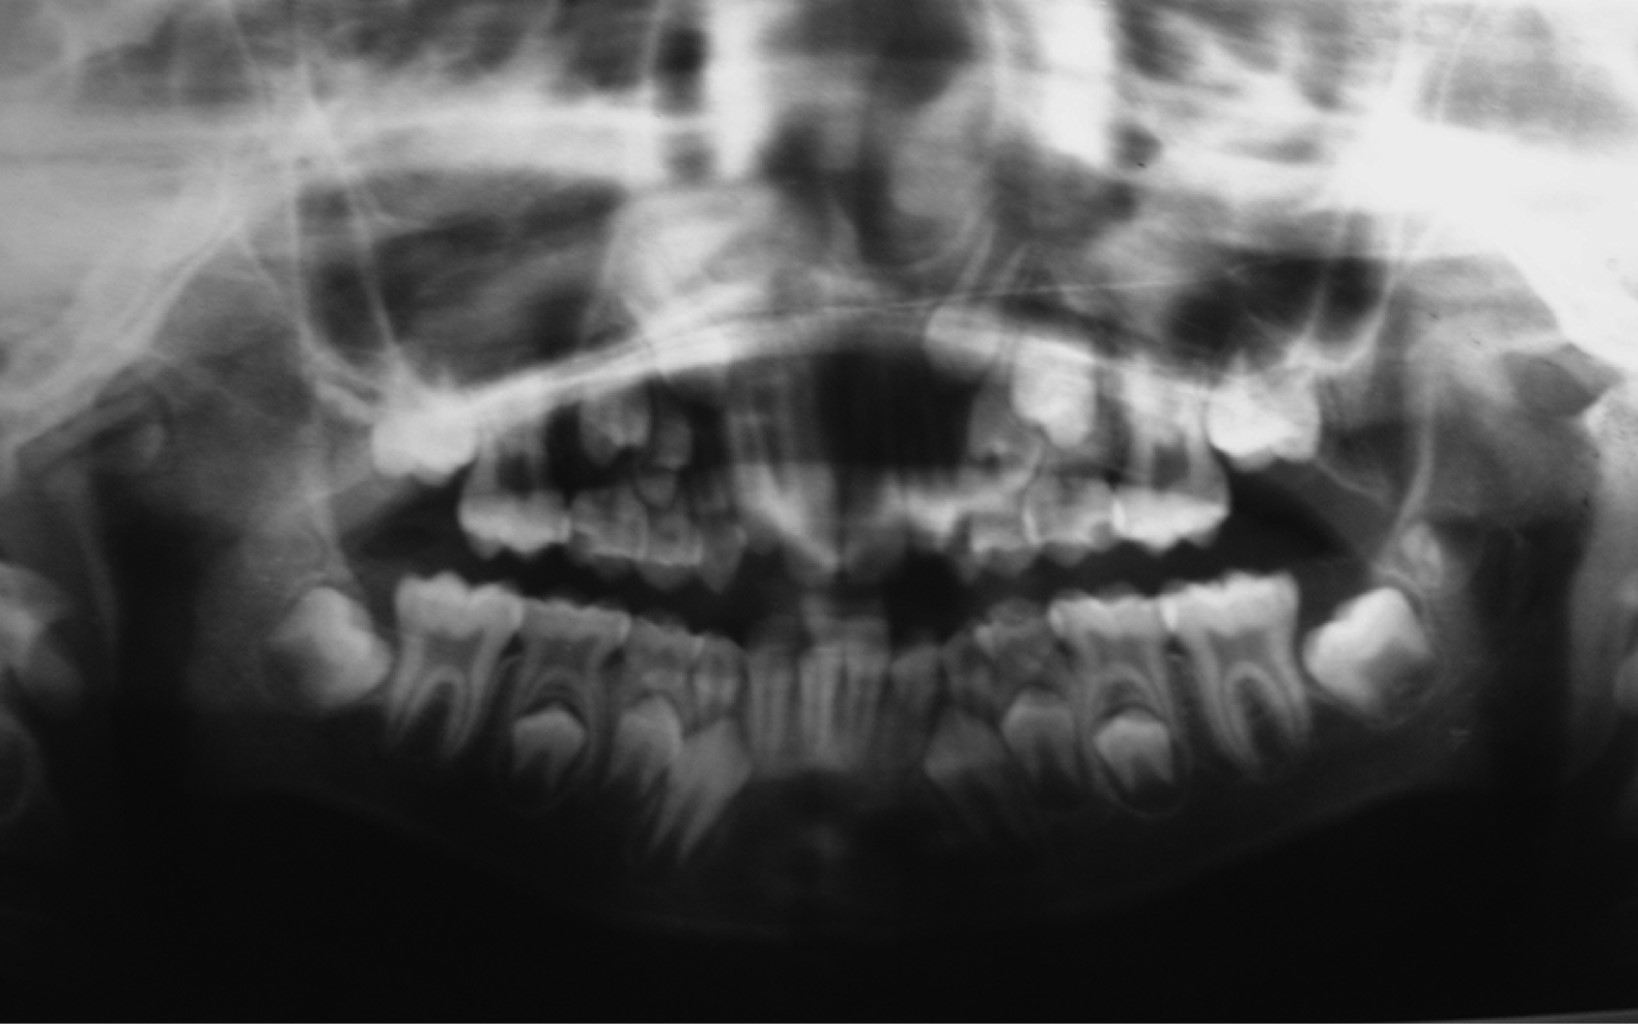

Se trata de paciente masculino de siete años de edad atendido en la Unidad Médica de Alta Especialidad (UMAE) No. 71 del Instituto Mexicano del Seguro Social, en la ciudad de Torreón, Coahuila, México. Acude por presentar imposibilidad de la apertura bucal desde la edad de cinco años, teniendo como único antecedente de importancia traumatismo facial al estar jugando y caer de su propia altura, evolucionando con progresiva limitación de apertura bucal hasta no poder abrirla en lo absoluto. A la exploración física, nula apertura bucal, aspecto facial con mínima alteración estética, micrognatia mandibular sin impacto estético importante (Figura 1). La radiografía inicial muestra anquilosis temporomandibular bilateral (Figura 2). Bajo anestesia general, intubación nasal con fibroscopio, se realiza liberación bilateral de anquilosis temporomandibular eliminando fragmentos óseos anquilosados y colocando prótesis metálicas de cavidad glenoidea de aleación cromo, cobalto, molibdeno (Figura 3), logrando adecuada apertura bucal sin complicaciones qué comentar (Figura 4). A la edad de 11 años se colocan prótesis metálicas de cóndilo de manera bilateral del mismo metal y mentoplastia de avance. Radiografía del paciente a la edad de 23 años (Figura 5).

Figura 2